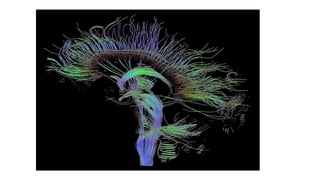

Tractography